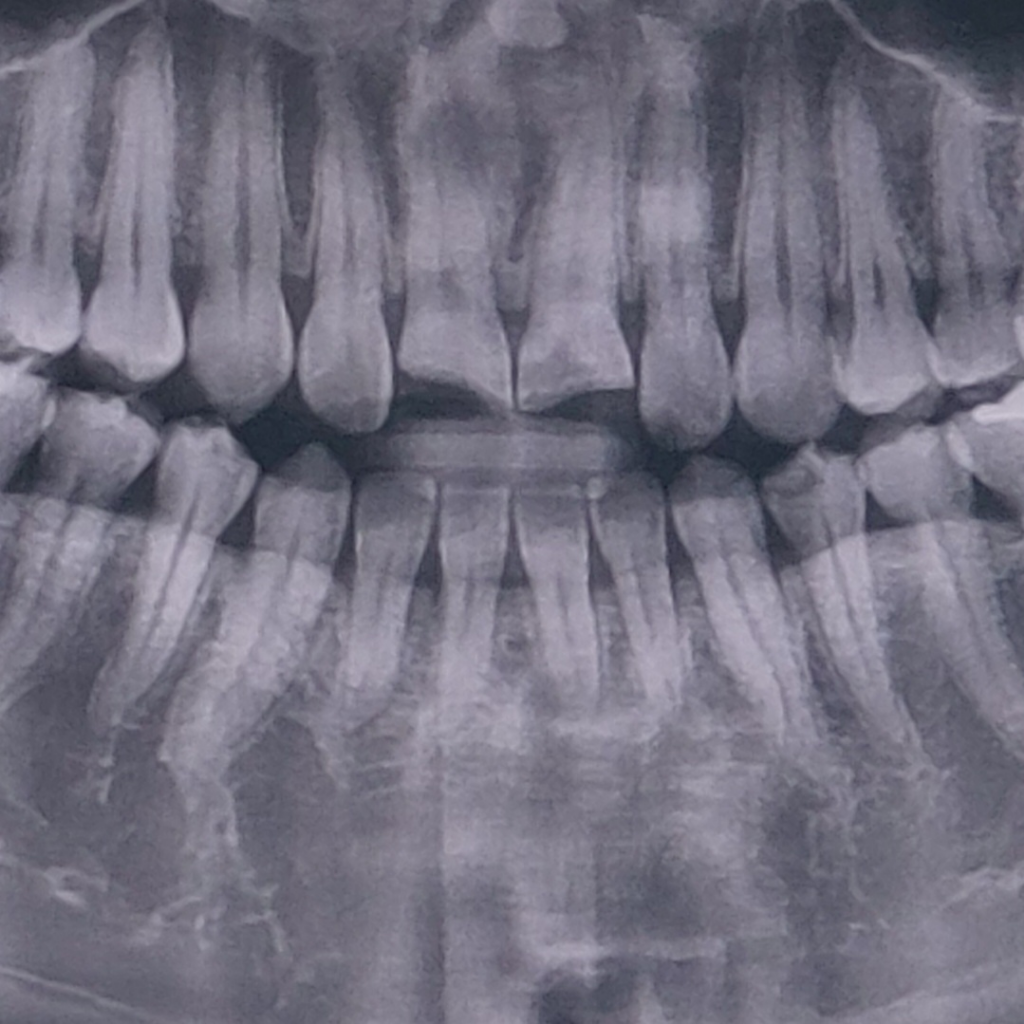

앞니 파절로 신경치료 완료후. 보존과 vs 보철과?

앞니 두개가 똑! 하고 부러져 1/3정도 남았습니다.

파절 직후 가까운 야간진료 치과을 찾아 신경치료를 진행하고 3회만에 마무리를 했어요.

사진은 파절 직후 찍은 엑스레이입니다.